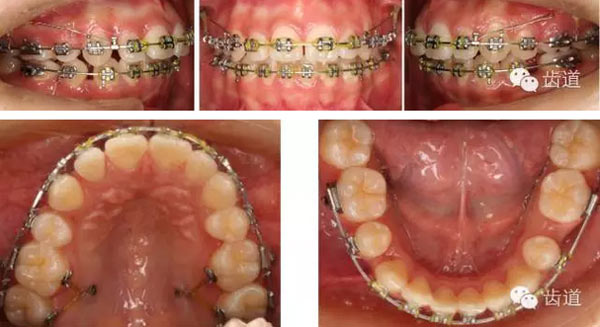

矯治過(guò)程